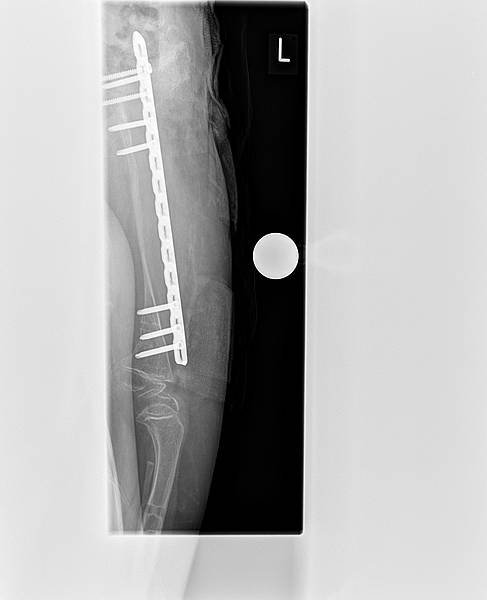

Unsere Ärzte trauten sich aufgrund der dünne des Knochens und der vorangegangenen Komplikationen nicht an die Entfernung des Fixateurs, so dass eine erneute Operation duch den Amerikaner notwendig wurde. Er hat den externen Fixateur am 01.10.2012 operativ entfernt und stabilisierte den Oberschenkel mit einer speziellen Lochplatte. Im oberen Oberschenkelbereich fixierte er diese mit 5 Schrauben, im unteren Oberschenkelbereich mit 3 Schrauben. Lea darf nun insgesamt 7 Wochen nicht belasten. Nur Liegen und Sitzen.

Am 18.11. kommen wir wieder nach Vogtareuth. Am 19.11. gibt es eine Röntgenkontrolle. Nach Freigabe durch den amerikanischen Spezialisten und unseren Ärzten hier, wird dann mit der Mobilisierung begonnen. Sobald sich der Knochen dann genug aufgebaut hat, wird die Lochplatte entfernt und der Knochen zunächst mit Drähten oder Nägeln stabilisiert. Diese werden dann auch irgendwann später wieder entfernt.